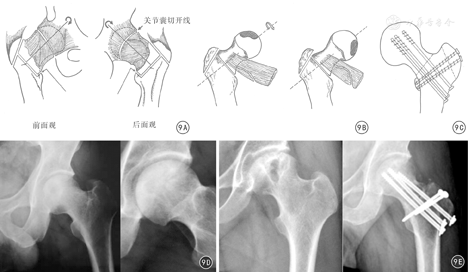

Sugioka[26]于1978年设计了针对早期股骨头坏死的股骨颈基底部旋转截骨术,后经多人改良,但保髋的临床效果参差不齐(图9A,图9B,图9C)。张洪等[27]在对股骨头血运充分掌握的基础上,再次进行了改良,对北美骨循环协会(Association Research Circulation osseous, ARCO)Ⅱ期和ⅢA、ⅢB期的患者,先通过SHD行股骨颈软组织瓣延长,再进行股骨颈基底部旋转截骨手术,使股骨头可以向前旋转、也可以向后旋转90°~180°,将股骨头坏死区域旋转到非负重区,取得更大更灵活的旋转角度,避免股骨头血运进一步损害,避免股骨头的塌陷,从而取得长期的保髋治疗效果(图9D、图9E)。